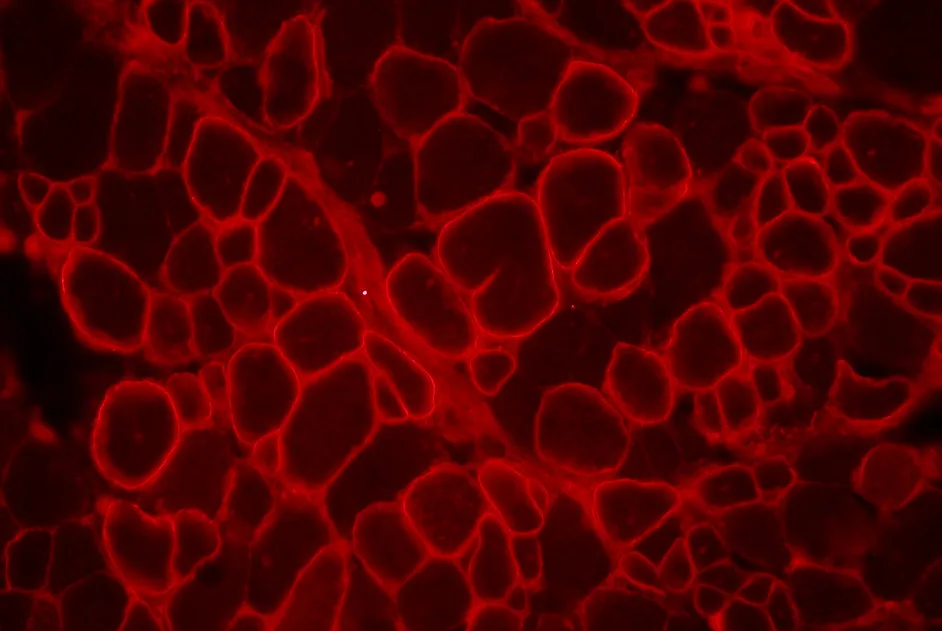

Une équipe anglaise a établi une corrélation entre l’IRM et l’histologie musculaire dans la dystrophie de Duchenne